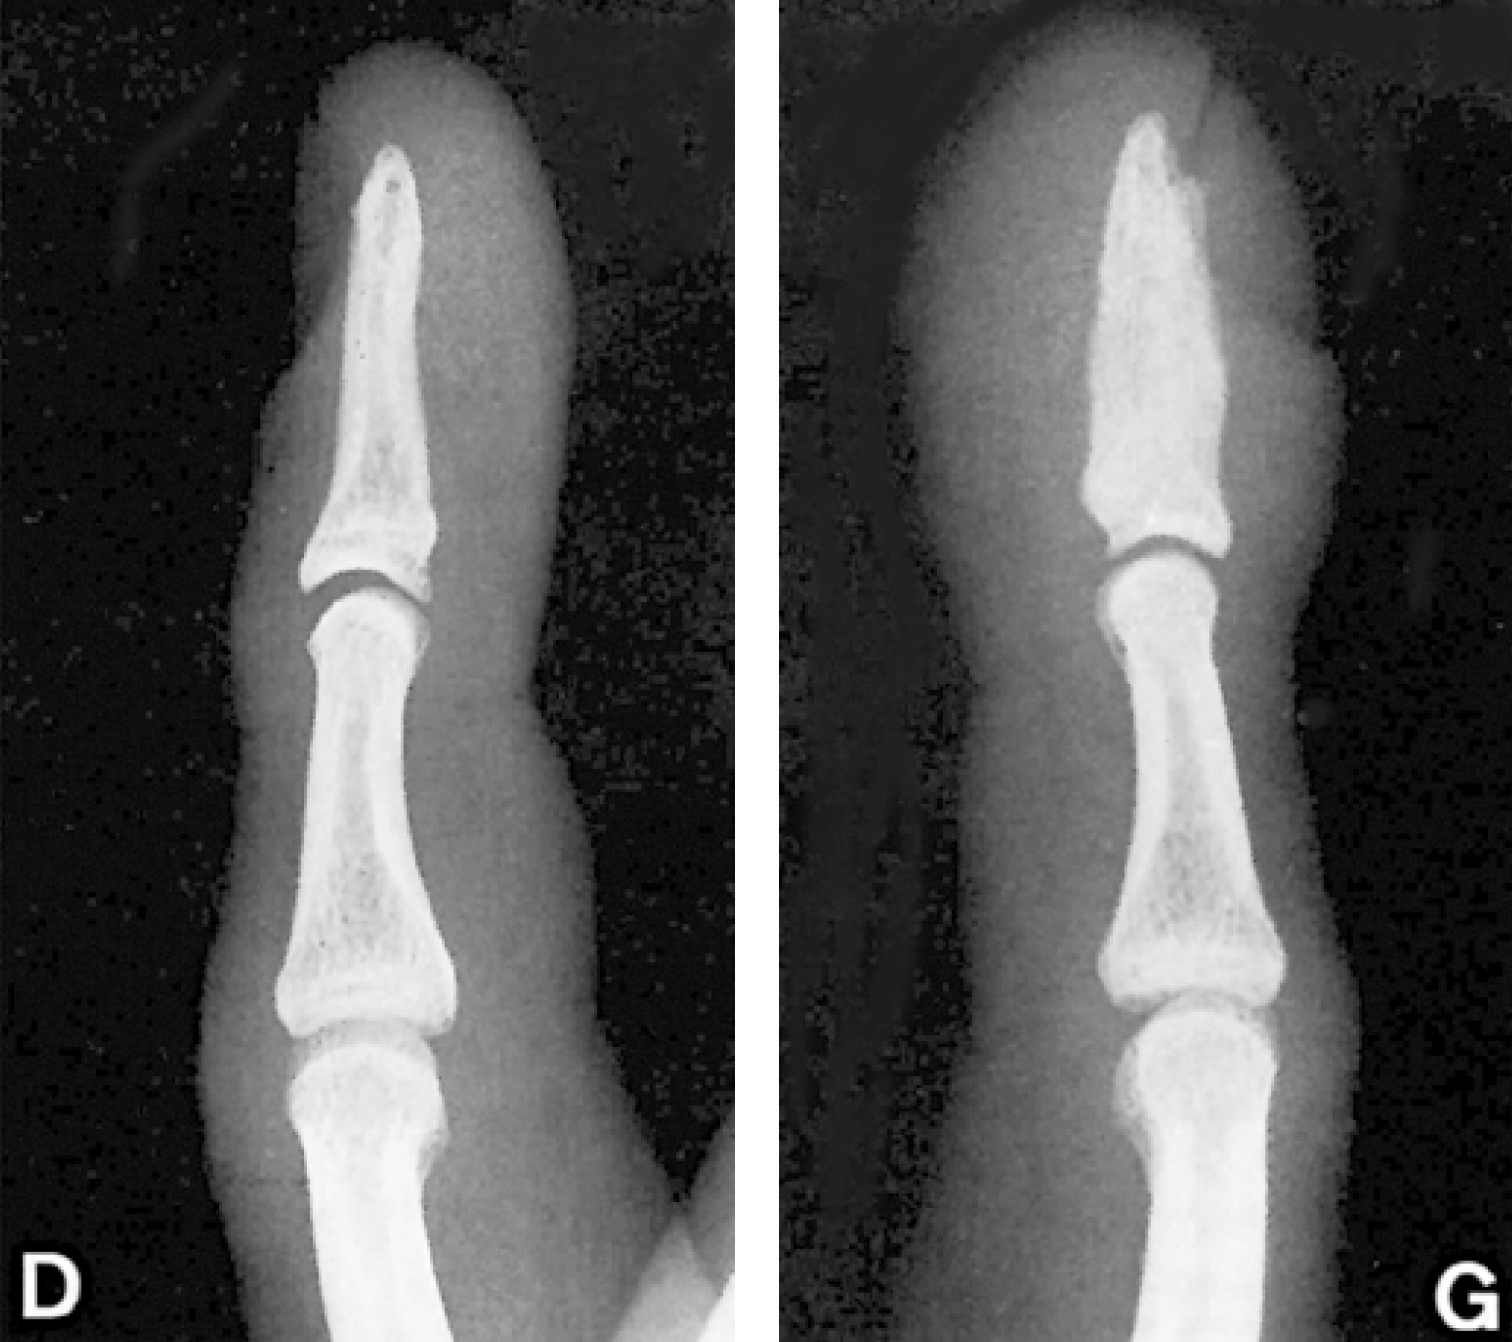

Figure 3.7. Des radiographies de profil comparatives des 5e doigts chez cet homme de 20 ans montrent, du côté gauche (G), un gonflement distal des tissus mous avec hypertrophie unguéale. Cet hippocratisme monodi-gital était progressif et totalement indolore depuis 10 ans et devenu dou-loureux depuis 6 mois.8

Figure 3.8. L'image radiographique en haute définition (a) de la pha-lange correspondante montre une hypertrophie osseuse plus marquée et plus inhomogène à son versant dorsal (têtes de flèches). Un exa-men TDM en coupe longitudinale directe (b) objective un épicentre nodulaire très dense (flèche) suggérant la possibilité d'un OO, qui fut confirmé histologiquement. Ces images ont été publiées en 1985 et cette image en scanner d'un OO phalangien était probablement la première de la littérature.